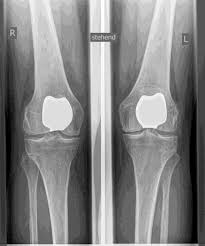

PROTHÈSE À GLISSIÈRE

L'arthroplastie partielle de l'articulation du genou est possible dans toutes les zones de l'articulation, mais elle est le plus souvent réalisée à l'intérieur de l'articulation du genou et est souvent appelée familièrement prothèse de traîneau. Semblable à la prothèse complète, le cartilage défectueux est remplacé par une nouvelle surface et un inlay en plastique est inséré entre les deux. Pour une prothèse partielle, toutes les structures ligamentaires, en particulier les ligaments croisés, doivent être en grande partie intactes.